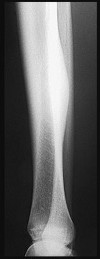

A 32-year-old male sustains a closed tibia fracture and develops intense leg pain out of proportion to the injury. You suspect acute compartment syndrome.

Which of the following pressure parameters is considered the most reliable threshold indication for performing a four-compartment fasciotomy?